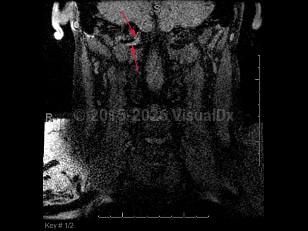

Vertebral artery dissection

Vertebral artery dissection (VAD) is splitting of the vertebral artery vessel wall, which can result in intramural hemorrhage / thrombus and expanding hematoma formation. This can lead to vessel occlusion or thromboembolism causing cerebellar and brainstem ischemia. Compromise of the vessel wall can also lead to subarachnoid hemorrhage. It is most commonly seen after a head or neck injury, including spinal manipulation, although it can occur spontaneously. It is an important cause of stroke in younger patients (under 50 years). The incidence of stroke in VAD has been estimated at 1%-8%.

Early symptoms can include occipital headache and neck pain. Focal neurological deficits related to vertebral artery territory ischemia can occur initially or after a latent period (usually within 3-7 days). These symptoms include ipsilateral facial numbness, contralateral body numbness, ataxia, nystagmus, vertigo, nausea / vomiting, dysarthria, dysphagia, hiccups, or ipsilateral Horner syndrome.

Prognosis is good overall but primarily hinges on the severity of the resulting ischemic event. If the VAD is complicated by thromboembolism, symptoms can include cortical vision loss and altered mental status. In acute cases, especially when accompanied by intracranial extension, mortality can approach 10%.